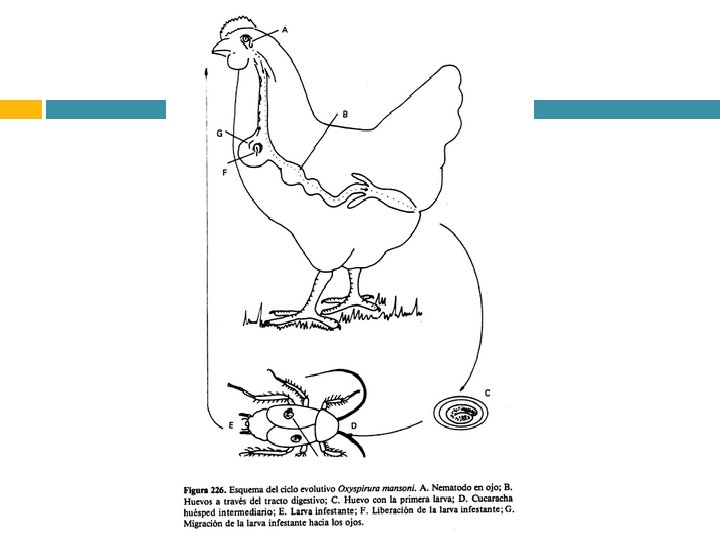

Parasitosis cutáneas y oculares Oxyspirura

Etiologia: Oxyspirura mansoni Oxyspirura parvorum Oxyspirura petrowi

Localizacion: • Membrana nictitante • Conducto nasolagrima l • Sacos conjuntivos

CB: Indirecto I Pycnoseleus surinamensis